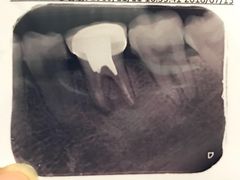

• 医疗健康 齿科 体检中心

口腔齿科 体检中心 医院 药店 中医 宠物医院 整形 妇幼医院 其他医疗